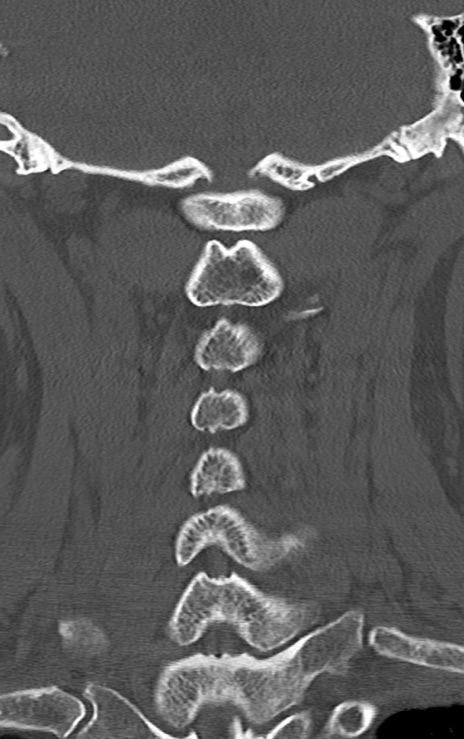

頚椎CT

矢状断像